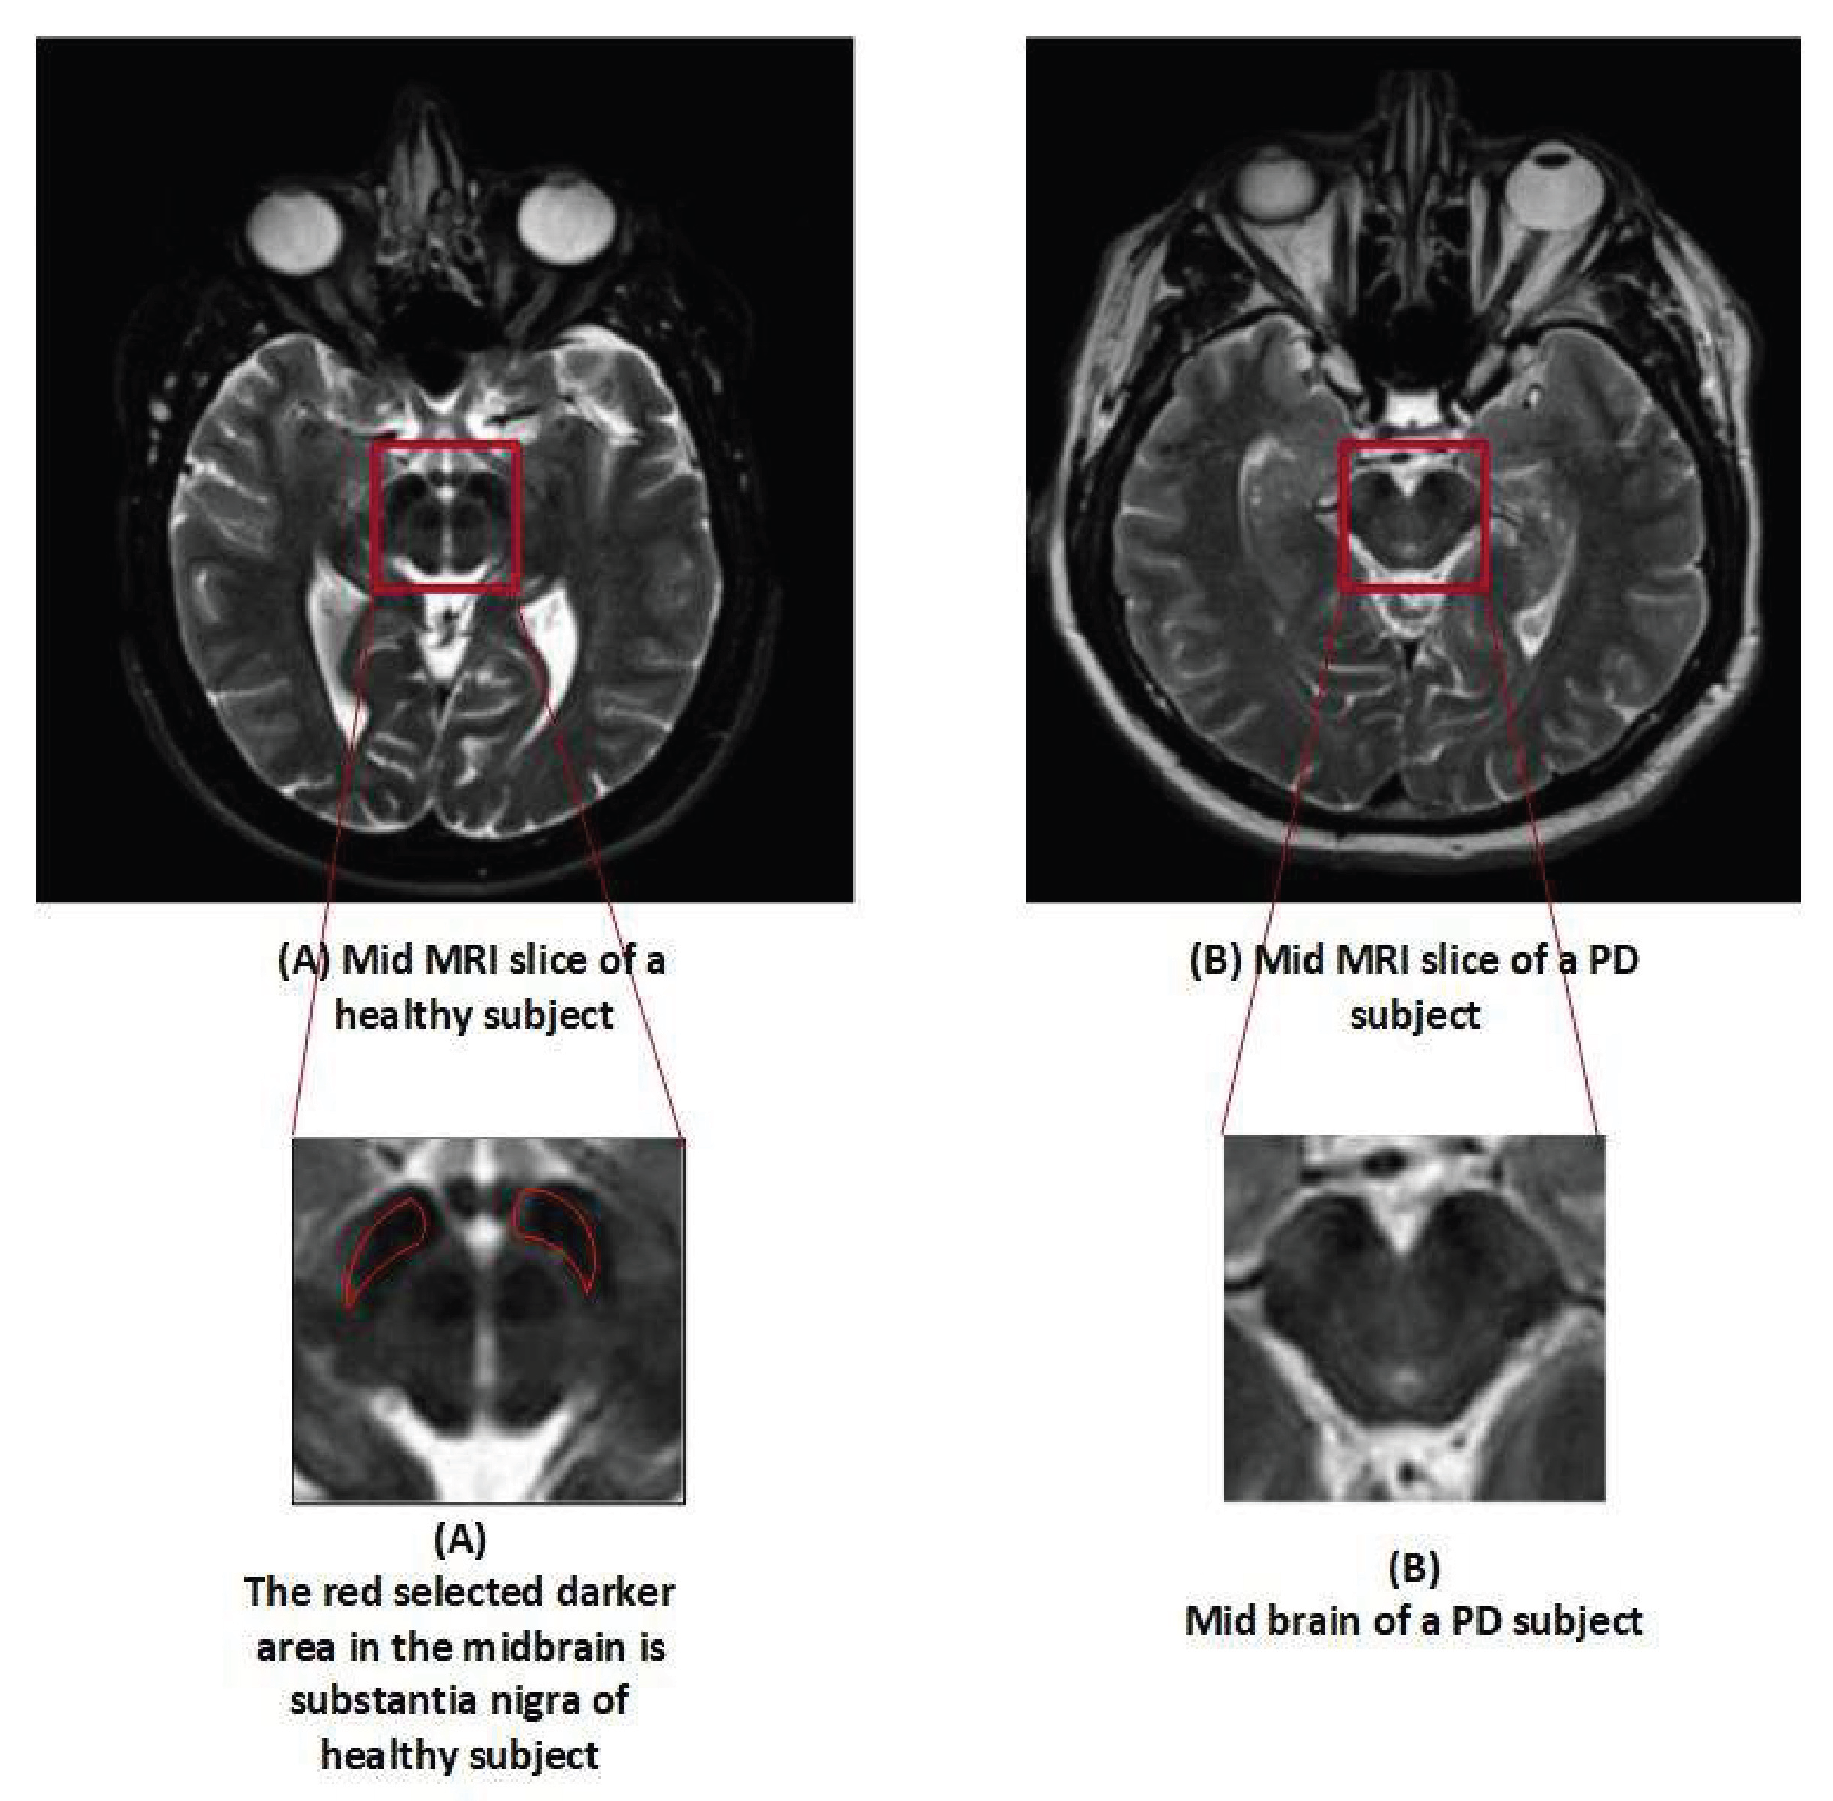

The dataset utilized in this analysis was made available by the PPMI. The PPMI is a multi-study facility with the goal of discovering trustworthy biomarkers and performing an early Parkinson’s disease diagnosis. Additionally, it is the project with the greatest data, which includes a sizable number of clinical, imaging, and biological samples. It is claimed that PPMI offers the largest dataset of its kind, and their samples are known as the benchmark of PD for research purposes across the globe [37]. A total of 500 samples (T2 weighted MR scan) were obtained in Digital Imaging and Communications in Medicine (DICOM) format with the followed parameters, Plane=AXIAL Acquisition Flip Angle = 150.0 degree, Matrix X = 228.0 pixels, Matrix Y = 256.0 pixels, Matrix Z = 54.0, Slice Thickness = 6.0 mm, Pulse Sequence=Spin echo, Pixel Spacing Y = 0.9375 mm, Pixel Spacing X = 0.9375 mm. The data contained 250 numbers of PD and 250 HC samples, balanced data. Dataset is used in such a way that 70% is used for training, 20% for testing, while 10% for validation. The dataset is available on (http://www.ppmi-info.org). Table 2 represents the details of the subject in terms of gender and age, while Figure 2 shows the difference between the MRI scan of a healthy subject and Parkinson’s patient.

Figure 2.

Slices of an MRI scan of an HC and PD patient.

The MR images were initially stored in the DICOM format and then converted into JPEG using publicly available software known as DICOM to JPEG. Each subject’s data consisted of 45 slices, and only slice number 22 was collected per subject since this slice provides the accurate image of the substantia nigra in PD class. Substantia nigra is a structure in the mid-brain area that controls movement and motor coordination. Dopamine is a substance that is produced in this area and is employed as a signal transmitter. This sends signals about movement and coordination to the brain and other parts of the body. A stack was created by combining slice number 22 from all the subjects. To align the images, intensity-based image registration was carried out using the OpenCV library on the stack. Image registration is the procedure of lining up scans of the brain or other pertinent regions taken from people with Parkinson’s disease. Using image registration techniques, this alignment establishes the spatial relationship between the pictures, enabling a consistent and uniform analysis. By ensuring that the pictures are in a uniform coordinate system, image registration eliminates variances brought on by changes in patient placement or scanning procedures. The primary objective of image registration was to eliminate unwanted and irrelevant information, which could lead our model to learn unnecessary and redundant features. For obtaining a perfect image of substantia nigra, the mid-brain section was cropped using the freehand region of interest (ROI) technique with a window size of 33 × 33. Freehand ROI was used for cropping because the size of the specific organ varies in different patients, and, instead of using fix ROI cropping, the freehand region of interest (ROI) technique provides us better control in cropping the exact position of the organ. This image was the final input to the CNN model. Figure 3 provides a visual representation of the preprocessing steps.